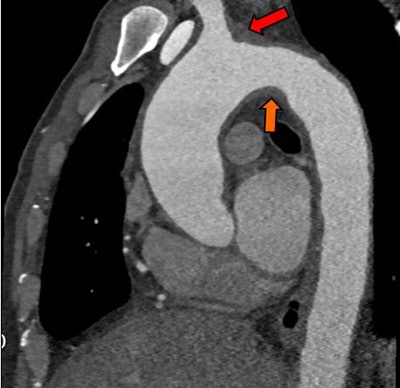

Above, an adult with indeterminate vasculitis that was unreported on echocardiography and seen on CT as mural aortic thickening (orange arrow) with extension into arch vessels (red arrow). Below, an adult with a left atrial appendage tip thrombus that was missed on CT and subsequently detected on echocardiography. The abnormality was noted on CT in retrospect (red arrow).Study limitations included its retrospective and single-center design. In addition, the researchers relied on echocardiography reports, and most of the echo was transthoracic echocardiography, Ajlan said.